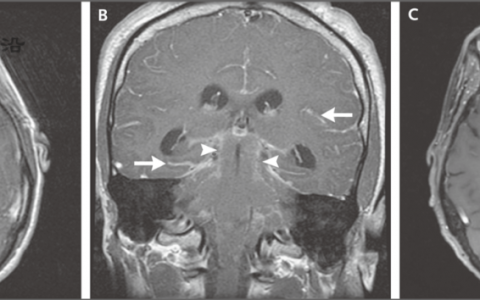

如上所述,在解读某些类型医学图像(如ECG、X线平片、计算机断层扫描[CT]和磁共振成像[MRI]扫描图像、皮肤图像和视网膜照片)方面,AI和机器学习已获得认可。在这些应用领域,AI和机器学习可标记出图像中的偏离常态之处,从而协助医护人员。

在本期杂志中,Lee等的一篇文章介绍了GPT-4聊天机器人及其在医学领域的应用。本文作者是一组研究人员,他们在开发GPT-4的公司工作,而GPT-4是接受过通识教育(包括医学知识)的聊天机器人。展望未来之前,快速回顾一下过去会很有助益。聊天机器人是一种计算机程序,它利用AI和自然语言处理方法理解问题,并自动回应,模拟人类对话。非常早期的医学聊天机器人ELIZA由麻省理工学院人工智能实验室Joseph Weizenbaum于1964—1966年开发(图3)。

图A显示非常早期医学聊天机器人ELIZA的屏幕截图,由麻省理工学院人工智能实验室Joseph Weizenbaum于1964—1966年开发。图B展示GPT-4的信息输入和输出,GPT-4是2023年推出的聊天机器人。BMI表示体质指数。